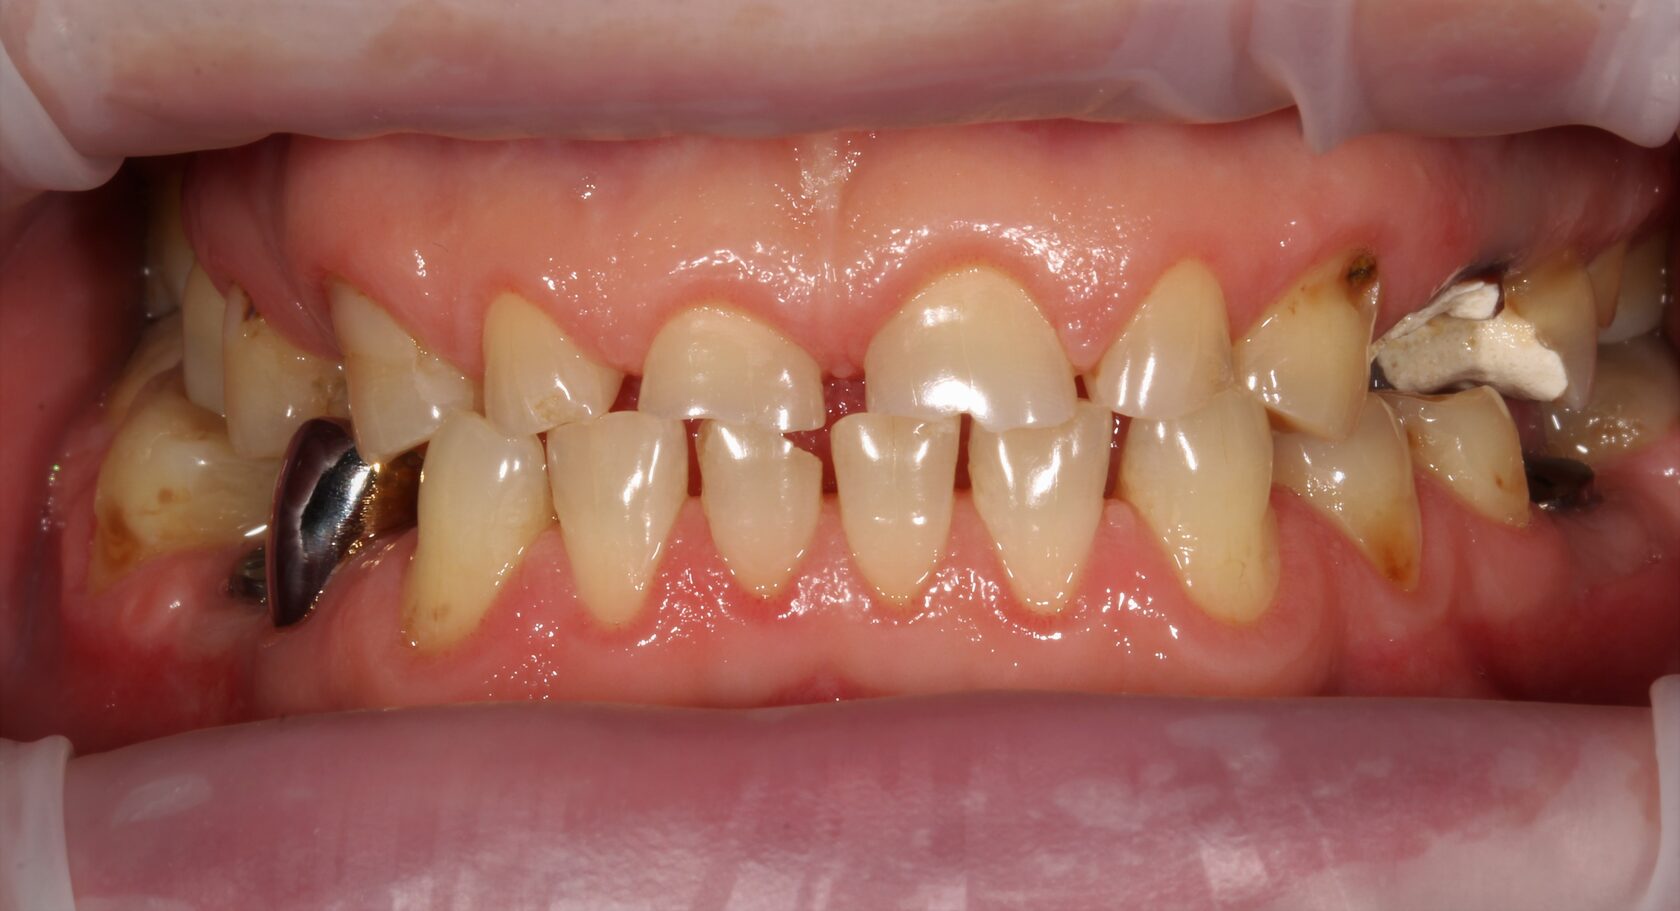

В данном клиническом случае представлена комплексная работа, состоящая из:

1 Терапевтический этап - лечение кариеса, подготовка корневых каналов и восстановление

культей зубов для установки коронок.

2 Хирургчий этап - удаление 2-х зубов с одномоментной дентальной имплантацией.

3 Сложное функционально-эстетическое протезирование (завышение прикуса на временных

коронках, стабилизация мышечного тонуса и позиции ВНЧС, перевод временных конструкций

в постоянные).

Длительность лечения составила более 1 год.